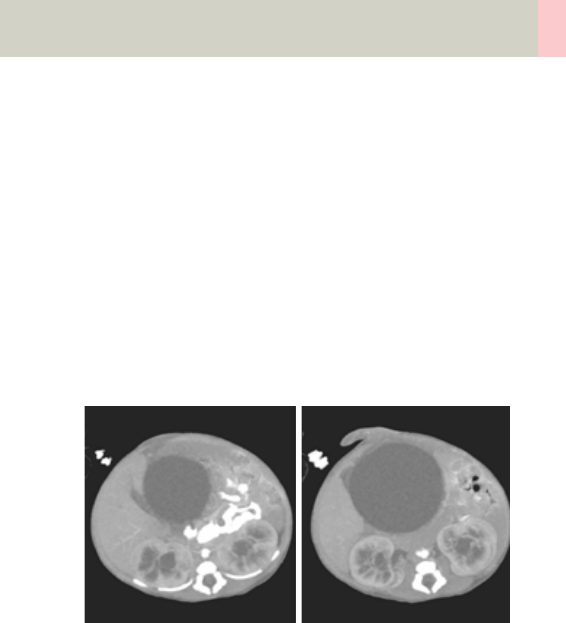

- C-Spine 298

- C-SpineVol 300

- SpineRoutine 302

- SpineThinSlice 304

- SpineVol 305

Contents

11

- SpineSeq 308

- Osteo 312

Pelvis 314

•Overview 314